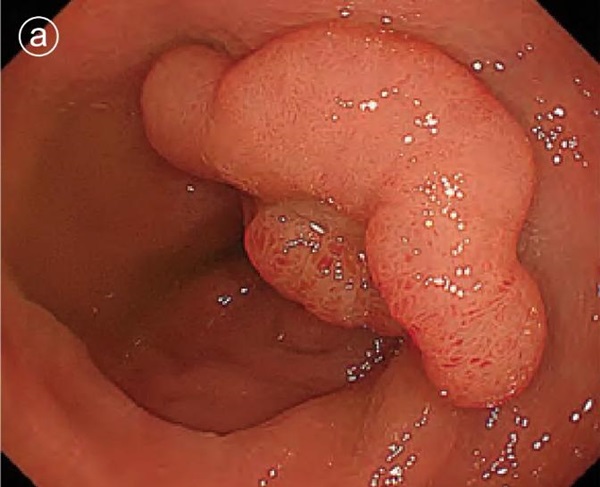

a. White light image

A 25 mm type IIa lesion with a slightly depressed central portion.